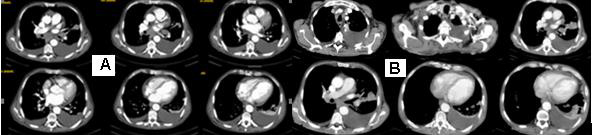

Tissue cylinders from lung biopsy composed of fusiform atypical cells with hyperchromic nuclei with characteristic perivascular arrangement and the presence of vorticity cellular pattern. Tumor cells are located among eosinophil hyalin-like stroma with the presence of intercytoplasmic vacuols and perinuclear halo, so most of them have signet-ring cell views. Tumor cells tightly infiltrate thin-walled vessels and places entering the lumen. In the lesion, thick-walled arterioles are also found. Tumor nuclei are polymorphs with visible nucleolus, cigar-shaped and blunt-ended with variable atypia, often with cytoplasmic vacuoles at both ends of nuclei (Figure 4).

Figure 4: Photomicrography of pulmonary biopsy composed of fusiform atypical cells with hyperchromic nuclei with perivascular arrangement and the presence of vorticity cellular pattern. Cells are located among eosinophil hyalin-like stroma with the presence of intercytoplasmic vacuols, so most of them have signet-ring cell views. The most common cells were spindle cells with elongated, blunt-ended, segmented or fusiform nuclei, and round/polygonal cells, often with rounded or indented nuclei A/ H&E: 400x; B/ H &E: 40x; C/ H&E:100x; D/ H&E:20x.